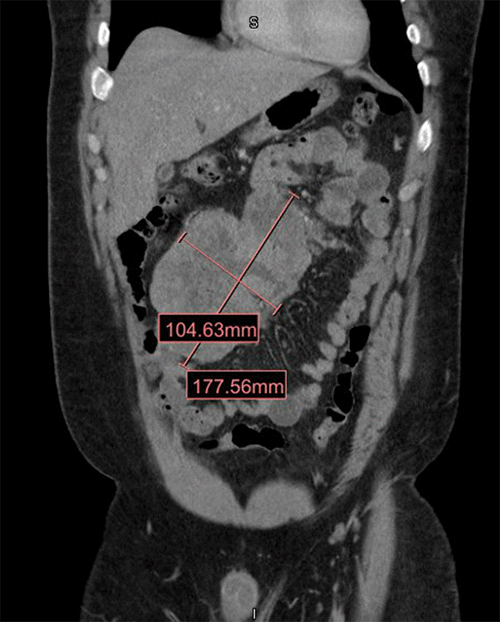

The patient's computed tomography (CT) scan of the abdomen and pelvis with contrast showed a large mass in the small bowel measuring 17 × 10 cm and thickened bowel wall (Figure 1). There was no evidence of bowel obstruction.

Figure 1. Abdominal CT in Coronal View Demonstrating Large Mass in Small Bowel. Published with Permission